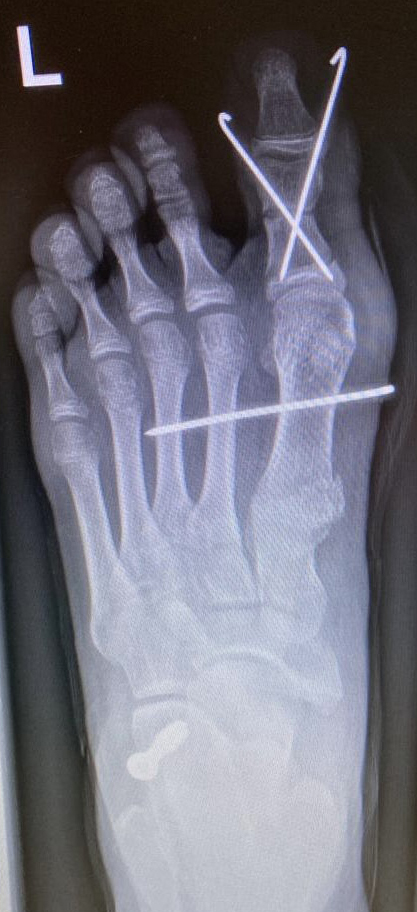

Zehenfehlstellungen

Im Rahmen von sub- oder superduktischen Zehen oder bei Vorhandensein einer Kirner-Deformität werden in unserem Team Kleinzehenkorrekturen entweder komplett oder inkomplett und sowohl am Grundglied kombiniert als auch am Mittelglied durchgeführt (Abb. 20).

Abb. 20 a-d: Krallenzehen mit subluxierter Gelenkstellung. Präoperatives Röntgenbild d. p. (a), intraoperative Nadelmarkierung für die entsprechenden Osteotomien (b); postoperatives Röntgenbild mit einer Multilevel-Korrektur der Zehen (c) und klinischer postoperativer Verlauf (d). In der letzten Aufnahme zeigt sich gut die bereits korrigierte Zehenstellung am rechten und die noch nicht versorgten Zehen am linken Fuß.

Werden komplette Osteotomien an den Zehen durchgeführt, fädeln wir die Osteotomien mit einem 1.2 oder 1.4 mm Kirschner-Draht auf, damit die einzelnen Fragmente nicht verkippen (Abb. 22).

Abb. 22 a-d: Präoperative Klauenzehen beim Jugendlichen in zwei Ansichten (a-b) und postoperative Auffädelung mit Kirschner-Drähten linker und rechter Fuß (c-d).